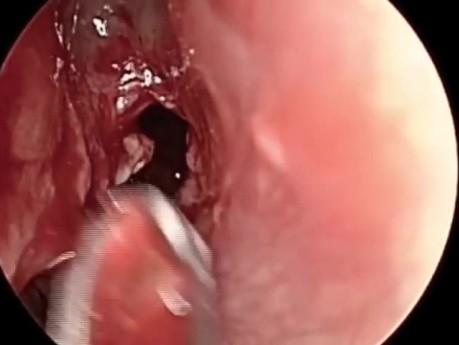

Endoskopowe usunięcie oponiaka rynienki węchowej

Klip przedstawia endoskopowe usunięcie oponiaka rynienki węchowej z następową rekonstrukcją płata nosowo-przegrodowego.